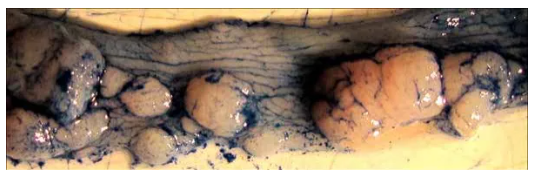

3. 处死后取小鼠结肠,可观察形成的肿瘤。值得注意的是,末端结肠/直肠肿瘤负荷较高(左上图),近端结肠肿瘤呈现褶皱状纹理(右上图),肿

瘤负荷很少。近距离观察末端结肠可观察到许多不同大小的肿瘤(下图)。

4. 使用阿新蓝染剂染色结肠,有助于观察到结肠内的纹理及肿瘤边界,能够精确测量肿瘤大小。